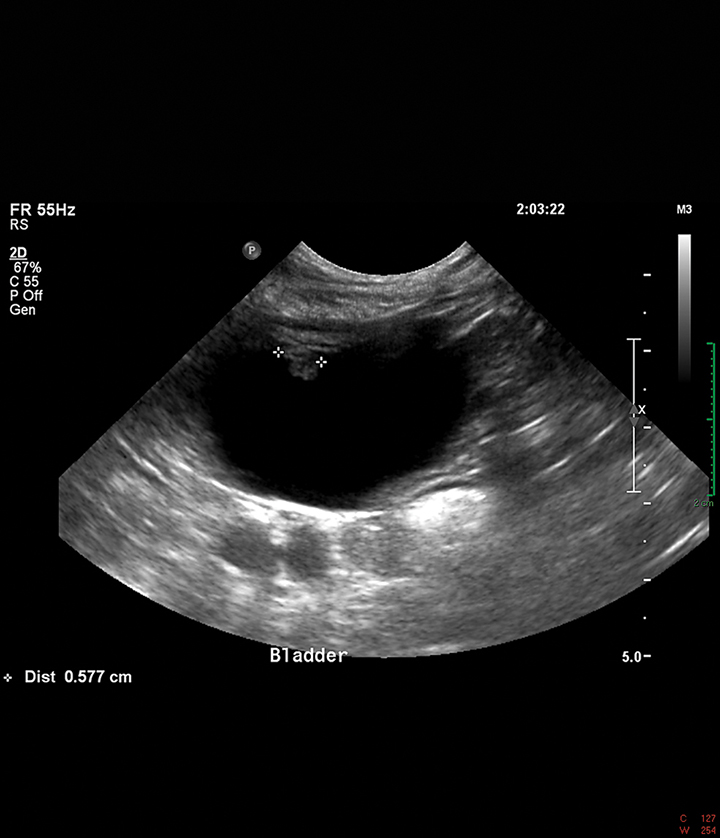

Pseudomembranous Cystitis An Uncommon Ultrasound Appearance of Cystitis in Cats and Dogs